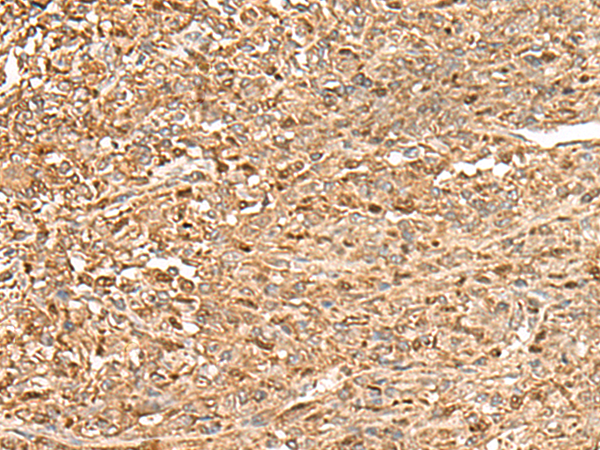

IHC positive control: |

Human liver cancer and Human cervical cancer |

IHC Recommend dilution: |

50-300 |